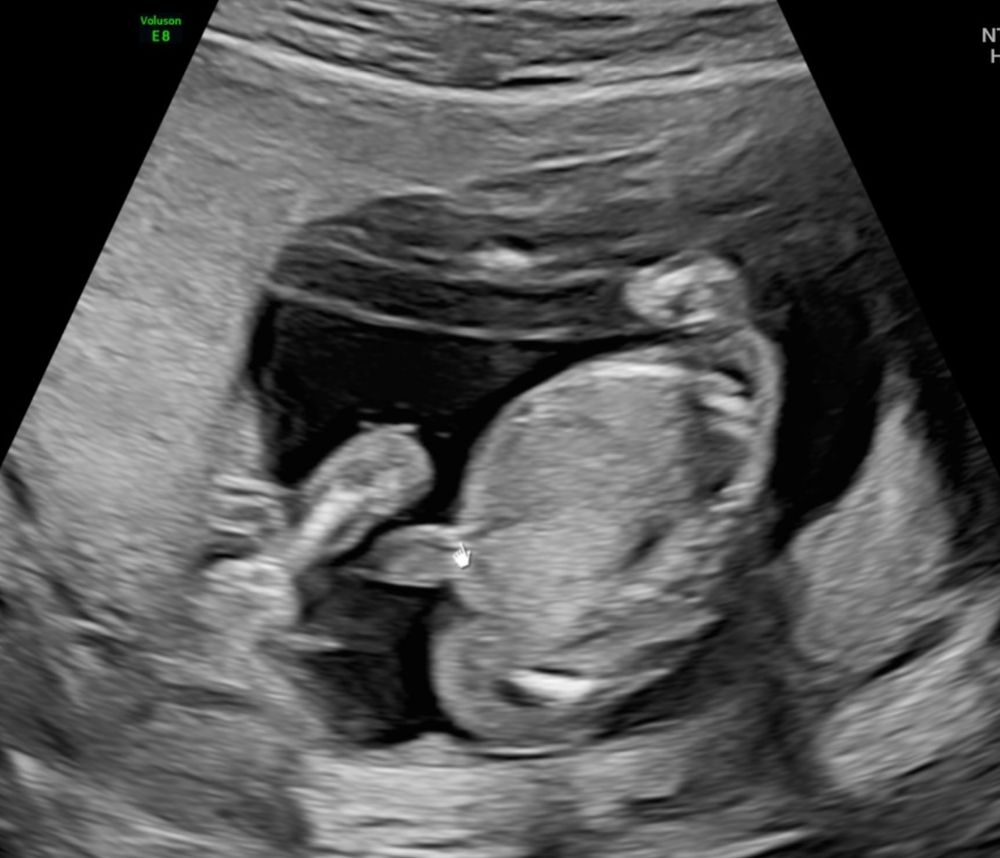

Девочки, угадываем пол 15 неделя

Пол малышаБыли на двух узи с разницей в неделю. Один врач сказал мальчик, другой - девочка

А вы что думаете?

А где мальчика то увидели? На первом девчонка вроде. А на втором я даже не разберу что. Если то что стрелочкой указано, то это пуповина, вроде бы. Но ракурс непонятный

Таня, это не ко мне вопрос где увидели. На втором фото то что стрелочкой указано это пуповина ну или нога. Она не имеет отношение к полу)) 😄

Анна, да , это у меня т9 сам дополнил. Вроде пуповина и даже переплетение видно. Рядом вроде как нога. В общем, ваш узист как художник, он так видит 😁